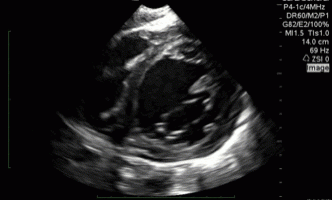

QA of the day. Foreshortened Apical 4 Chamber View. Flatten that probe #pocus #foamus #meded